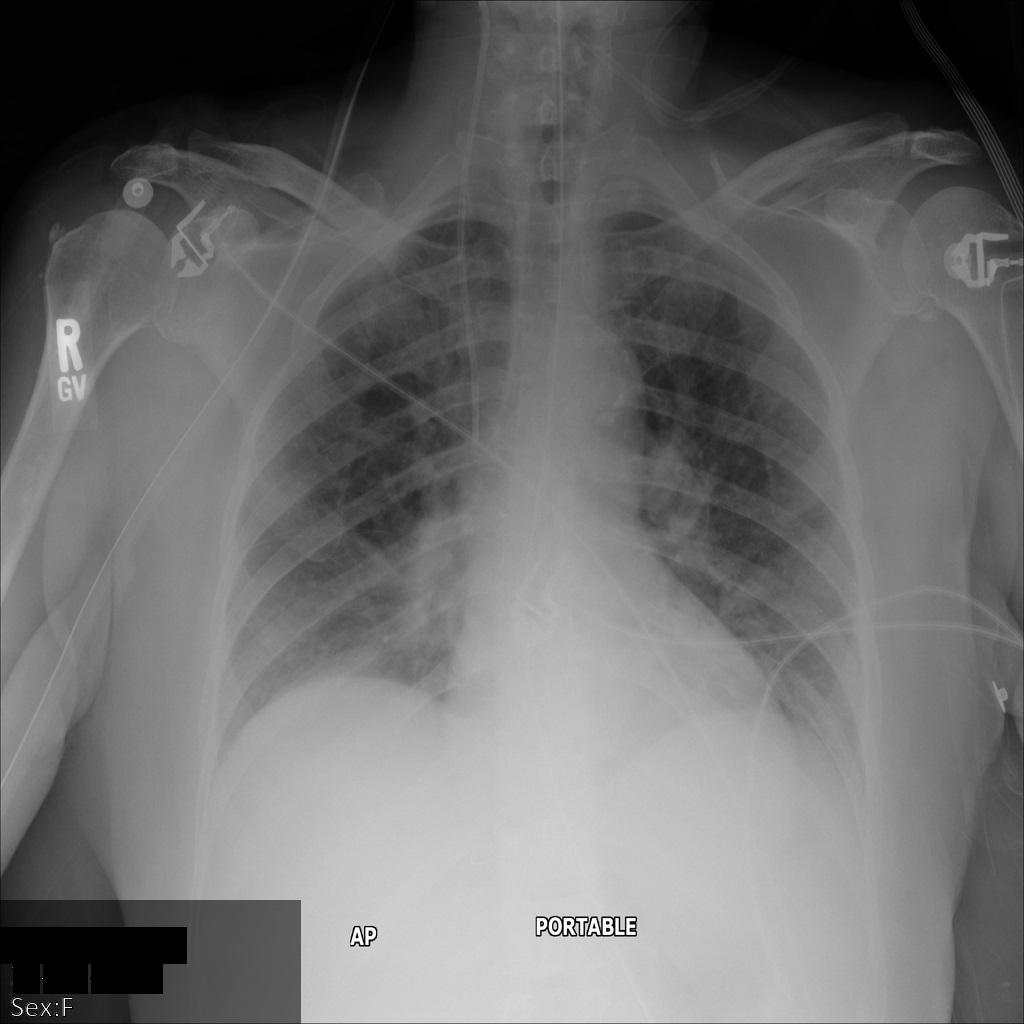

En la siguiente imagen, se muestra una radiografía sin ocultamiento de un paciente:

Después de enviar la imagen a la API de Cloud Healthcare mediante la opción REDACT_SENSITIVE_TEXT, la imagen aparece de la siguiente manera:

Puedes ver que ocurrió lo siguiente:

- Se ocultó el elemento

PERSON_NAMEen la esquina inferior izquierda de la imagen - Se ocultó el elemento

DATEen la esquina inferior izquierda de la imagen

El sexo del paciente no se ocultó porque no se considera texto sensible de acuerdo con los Infotipos de DICOM predeterminados.